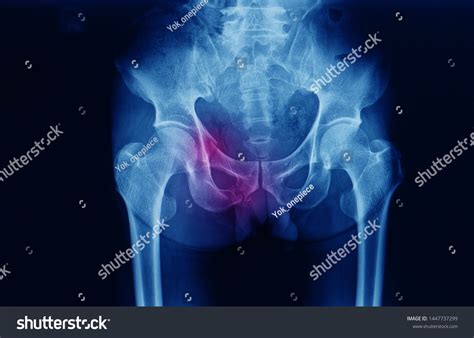

X-Rays

X-rays are often the first-line imaging modality for evaluating the inferior pubic ramus. They provide a clear view of the bone structure and can help identify fractures, dislocations, and other abnormalities. However, X-rays have limitations in visualizing soft tissue structures and may not always provide a detailed view of the bone.